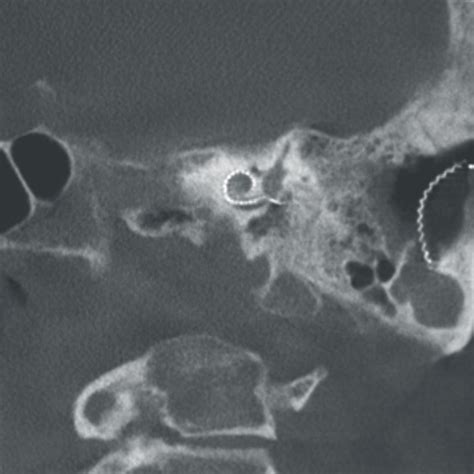

The field is constantly evolving, thanks to the integration of advanced technology. Many modern procedures now utilize endoscopic techniques, which involve thin, flexible tubes with cameras that allow surgeons to visualize the surgical site on a high-definition monitor. This approach has transformed an Ent Operation from a procedure requiring large, invasive incisions to one that is often performed through natural openings in the body.

Advancements like robotic-assisted surgery and image-guided navigation systems have significantly improved precision. These tools allow for safer access to sensitive areas near the brain, eyes, and major blood vessels. By choosing a facility that invests in these technologies, you are choosing a higher standard of care that prioritizes both efficacy and a faster return to your daily life.